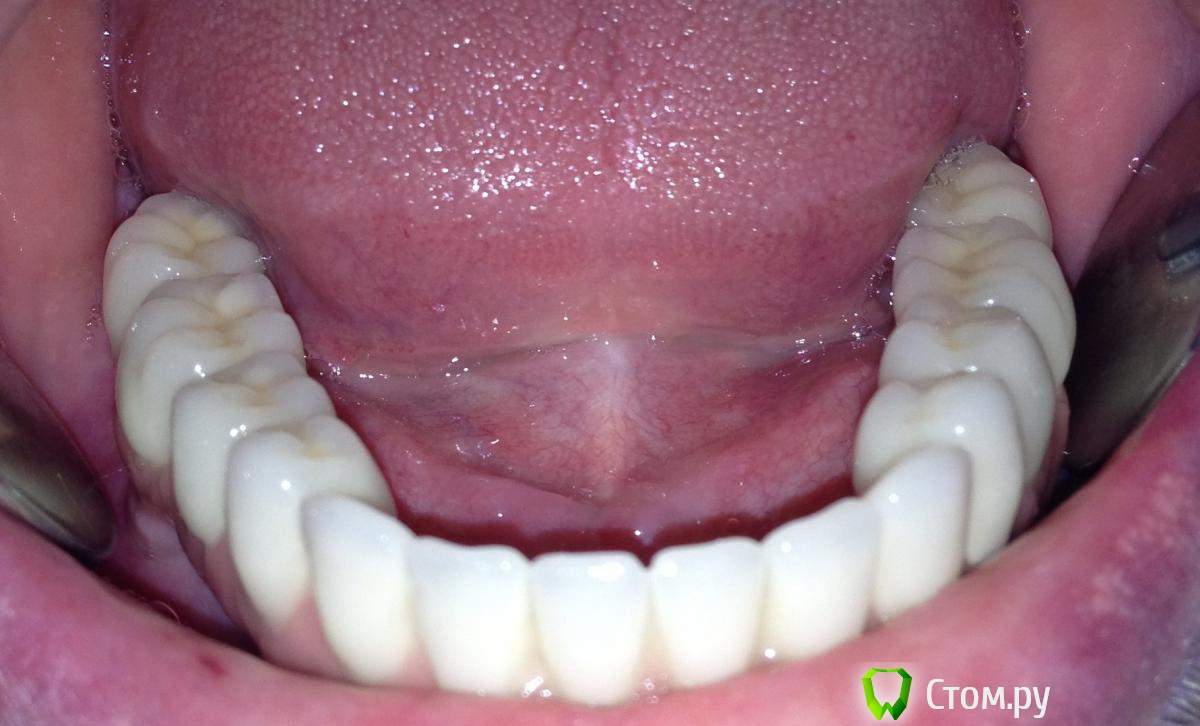

MaxDok Опубликовано 10 апреля, 2014 Автор Поделиться Опубликовано 10 апреля, 2014 Еще похожая работа 5 1 Ссылка на комментарий

MaxDok Опубликовано 11 апреля, 2014 Автор Поделиться Опубликовано 11 апреля, 2014 (изменено) Работа понравилась.Какая была временная конструкция? Слепок под постоянную конструкцию снимался с уровня абатмента? СпасибВременнная конструкция на временных титановых абатментах , обычная пластмассовая облицовка ,винтовая фиксация.Отттиск с уровня имплантов снимал , фото индивидуальной ложки и самого оттиска не могу найти. Изменено 11 апреля, 2014 пользователем MaxDok 6 Ссылка на комментарий